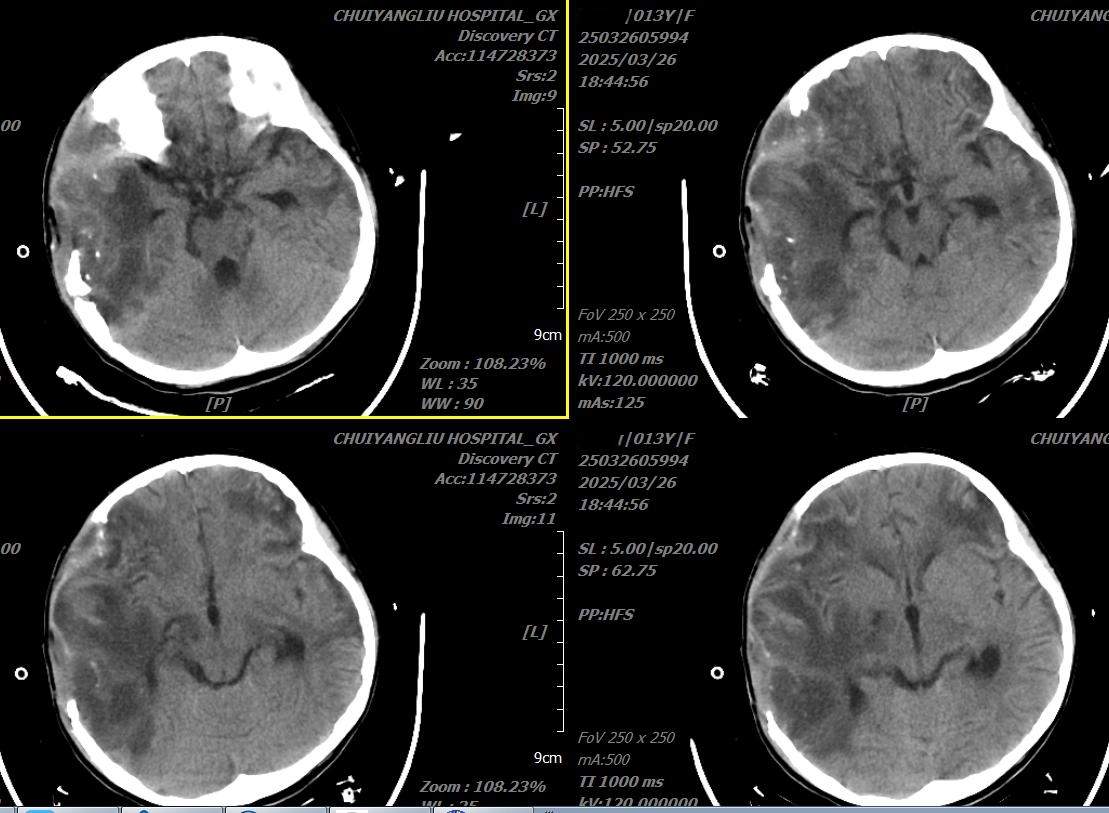

入院当日头颅CT

2025年3月26日,小雨转入医院神经外科时,体温达39.1℃,心率达145次/分,右侧颅骨手术后缺失状态,气管切开,带胃管、肠管,持续胃肠减压,静脉输营养液。无法自主排尿,带尿管。患儿可无意识睁眼,无法听指令运动。